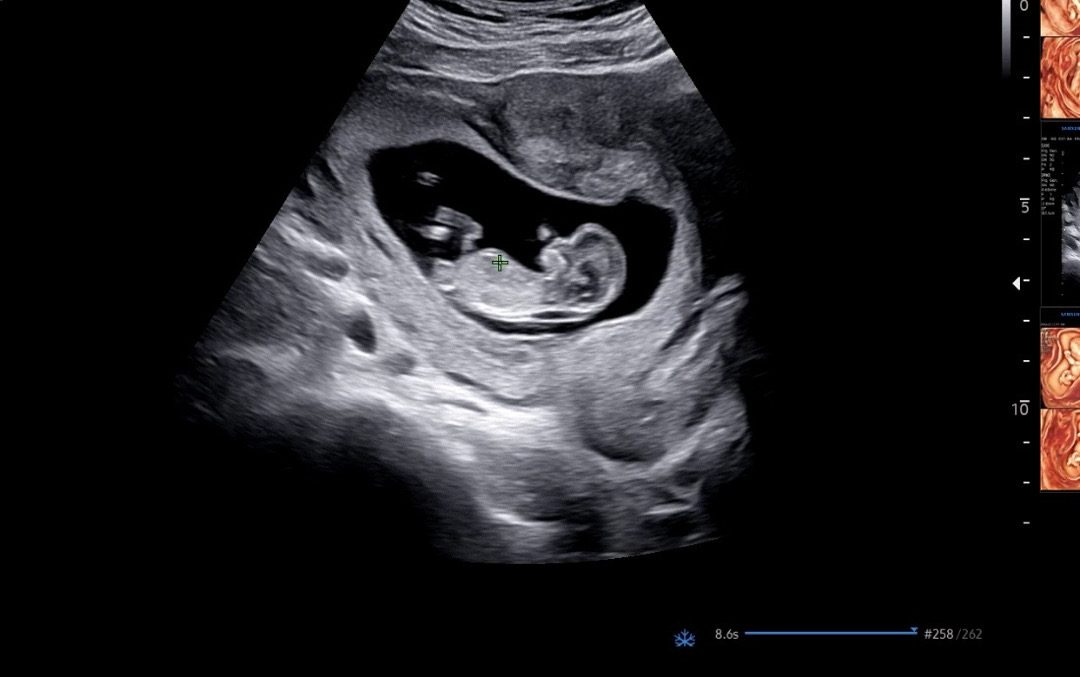

11주 각도법 투표 부탁드릴게요~~

11주 각도법 참견 부탁드릴게용🙏🏻